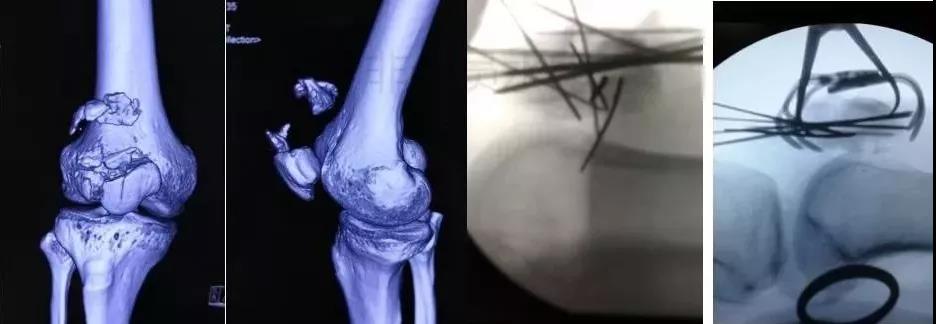

3)股骨远端骨折

- 开放性骨折,伤及腘动脉,坐骨神经,紧急手术,超膝关节外支架。

- 单纯闭合骨折,内固定:钢板或逆行髓内钉。